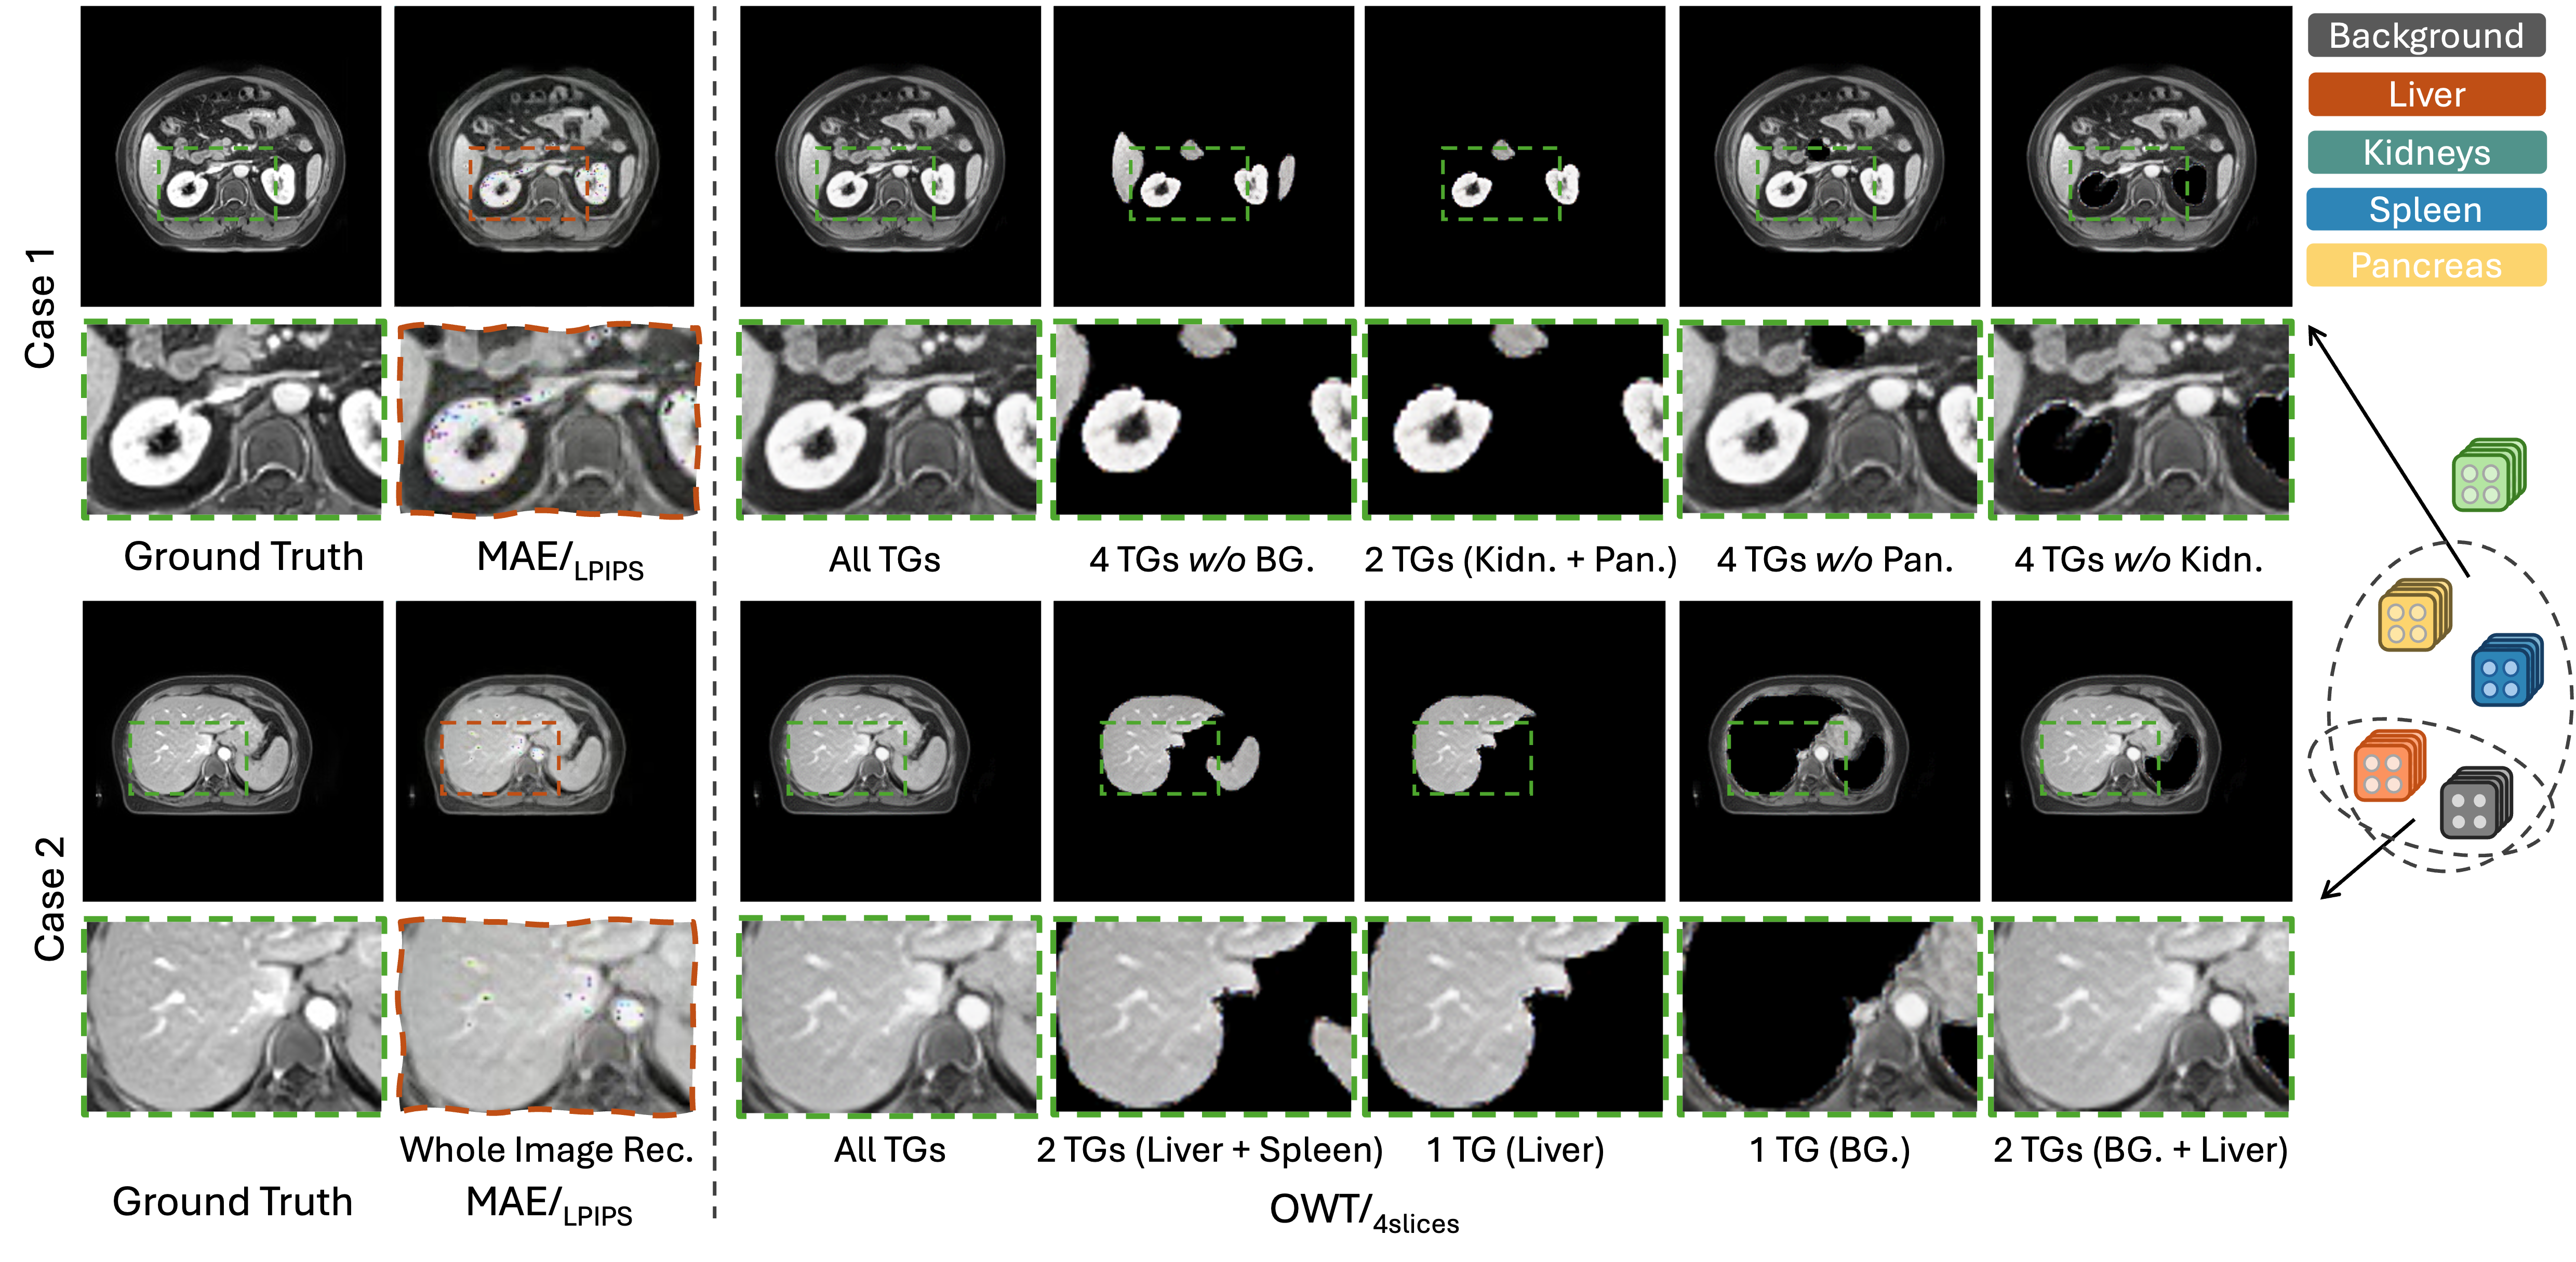

Refer to caption

Figure 4: Samples of holistic-based and semantic-based medical image reconstruction from an MRI dataset.

We further explore a semantic-based reconstruction scenario by retaining only a single organ-wise token group at a time, feeding it through AHER and the decoder to generate an organ-specific image. As reported in Tables 1 and 2, using a larger number of slices in CT and MRI volumes leads to more robust disentangled token groups, thereby improving semantic-based reconstruction quality. Fig. 4 illustrates MRI cases (rich in textural detail). Even with LPIPS added, MAE suffers from noticeable detail loss, whereas OWT (all token groups retained) produces sharper and clearer details. Additionally, we can freely combine the token groups to reconstruct only the content of interest.

In the zoom-in rows of Fig. 4, the liver/kidney reconstruction appears nearly identical whether we use only the liver/kidney token group or combine it with others, suggesting that OWT’s organ token groups are highly semantically independent. This property offers better interpretability as well as controllability, enabling reconstruction without unnecessary entanglement of unrelated organ features.